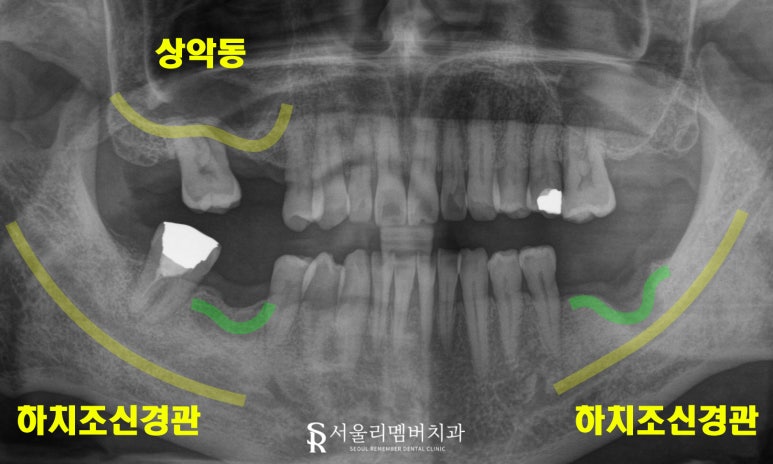

엑스레이 진단:

치조골 감소와 하치조신경 근접

엑스레이로 진단한 결과,

16번과 17번 부위는 치조골 양이 현저히 부족했으며,

상악동부위 까지 내려와 있었습니다.

하악의 46번과 36번 부위는

치조골이 움푹 꺼져 있었고,

하치조신경과도 가까운 모습이었죠.

또한, 47번은 오래된 보철의 수명이 다한 모습으로

교합평면 위치도 바람직하지 않았습니다.